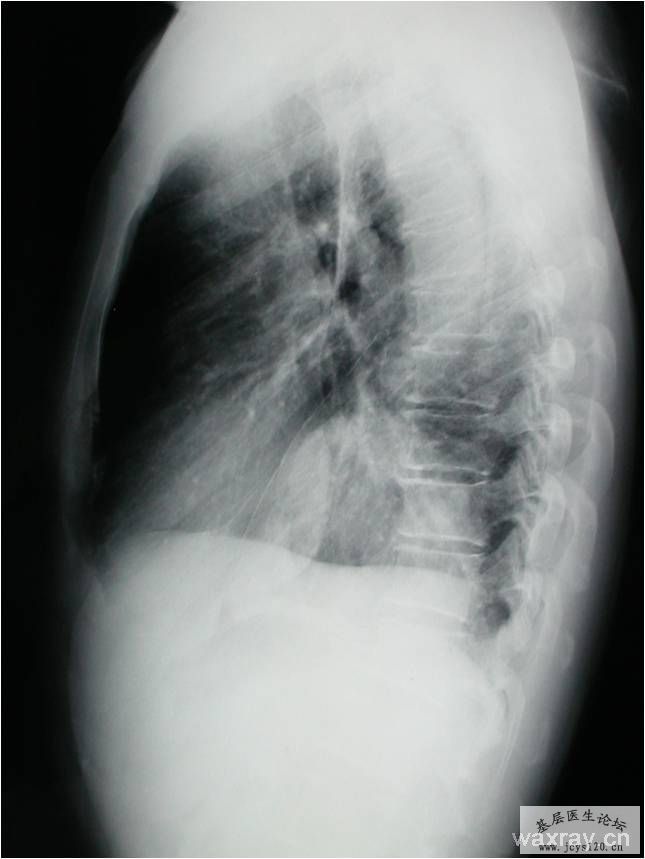

男,55岁,反复咳嗽2月余;2个月前无明显诱因出现咳嗽,无发热、咳痰、胸痛,无夜间盗汗、乏力等症状